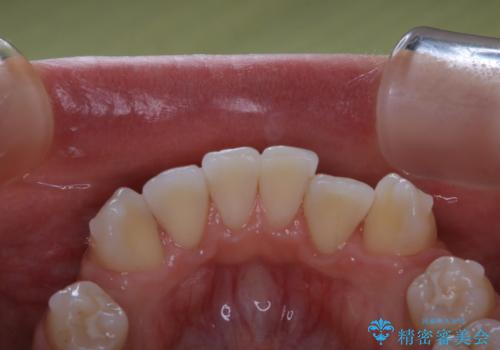

- インビザラインでのマウスピース矯正中に着色が気になるとのことでした。着色が全体的に付着していたためPMTC60分コースを行いました。

またPMTCを行うことで、ご自身本来の歯の色になり自然な明るさになります。

口元が自然な明るさになることで、より清潔感のある印象になるため結婚式・行事やイベント前などにもPMTCを行うはおすすめです。